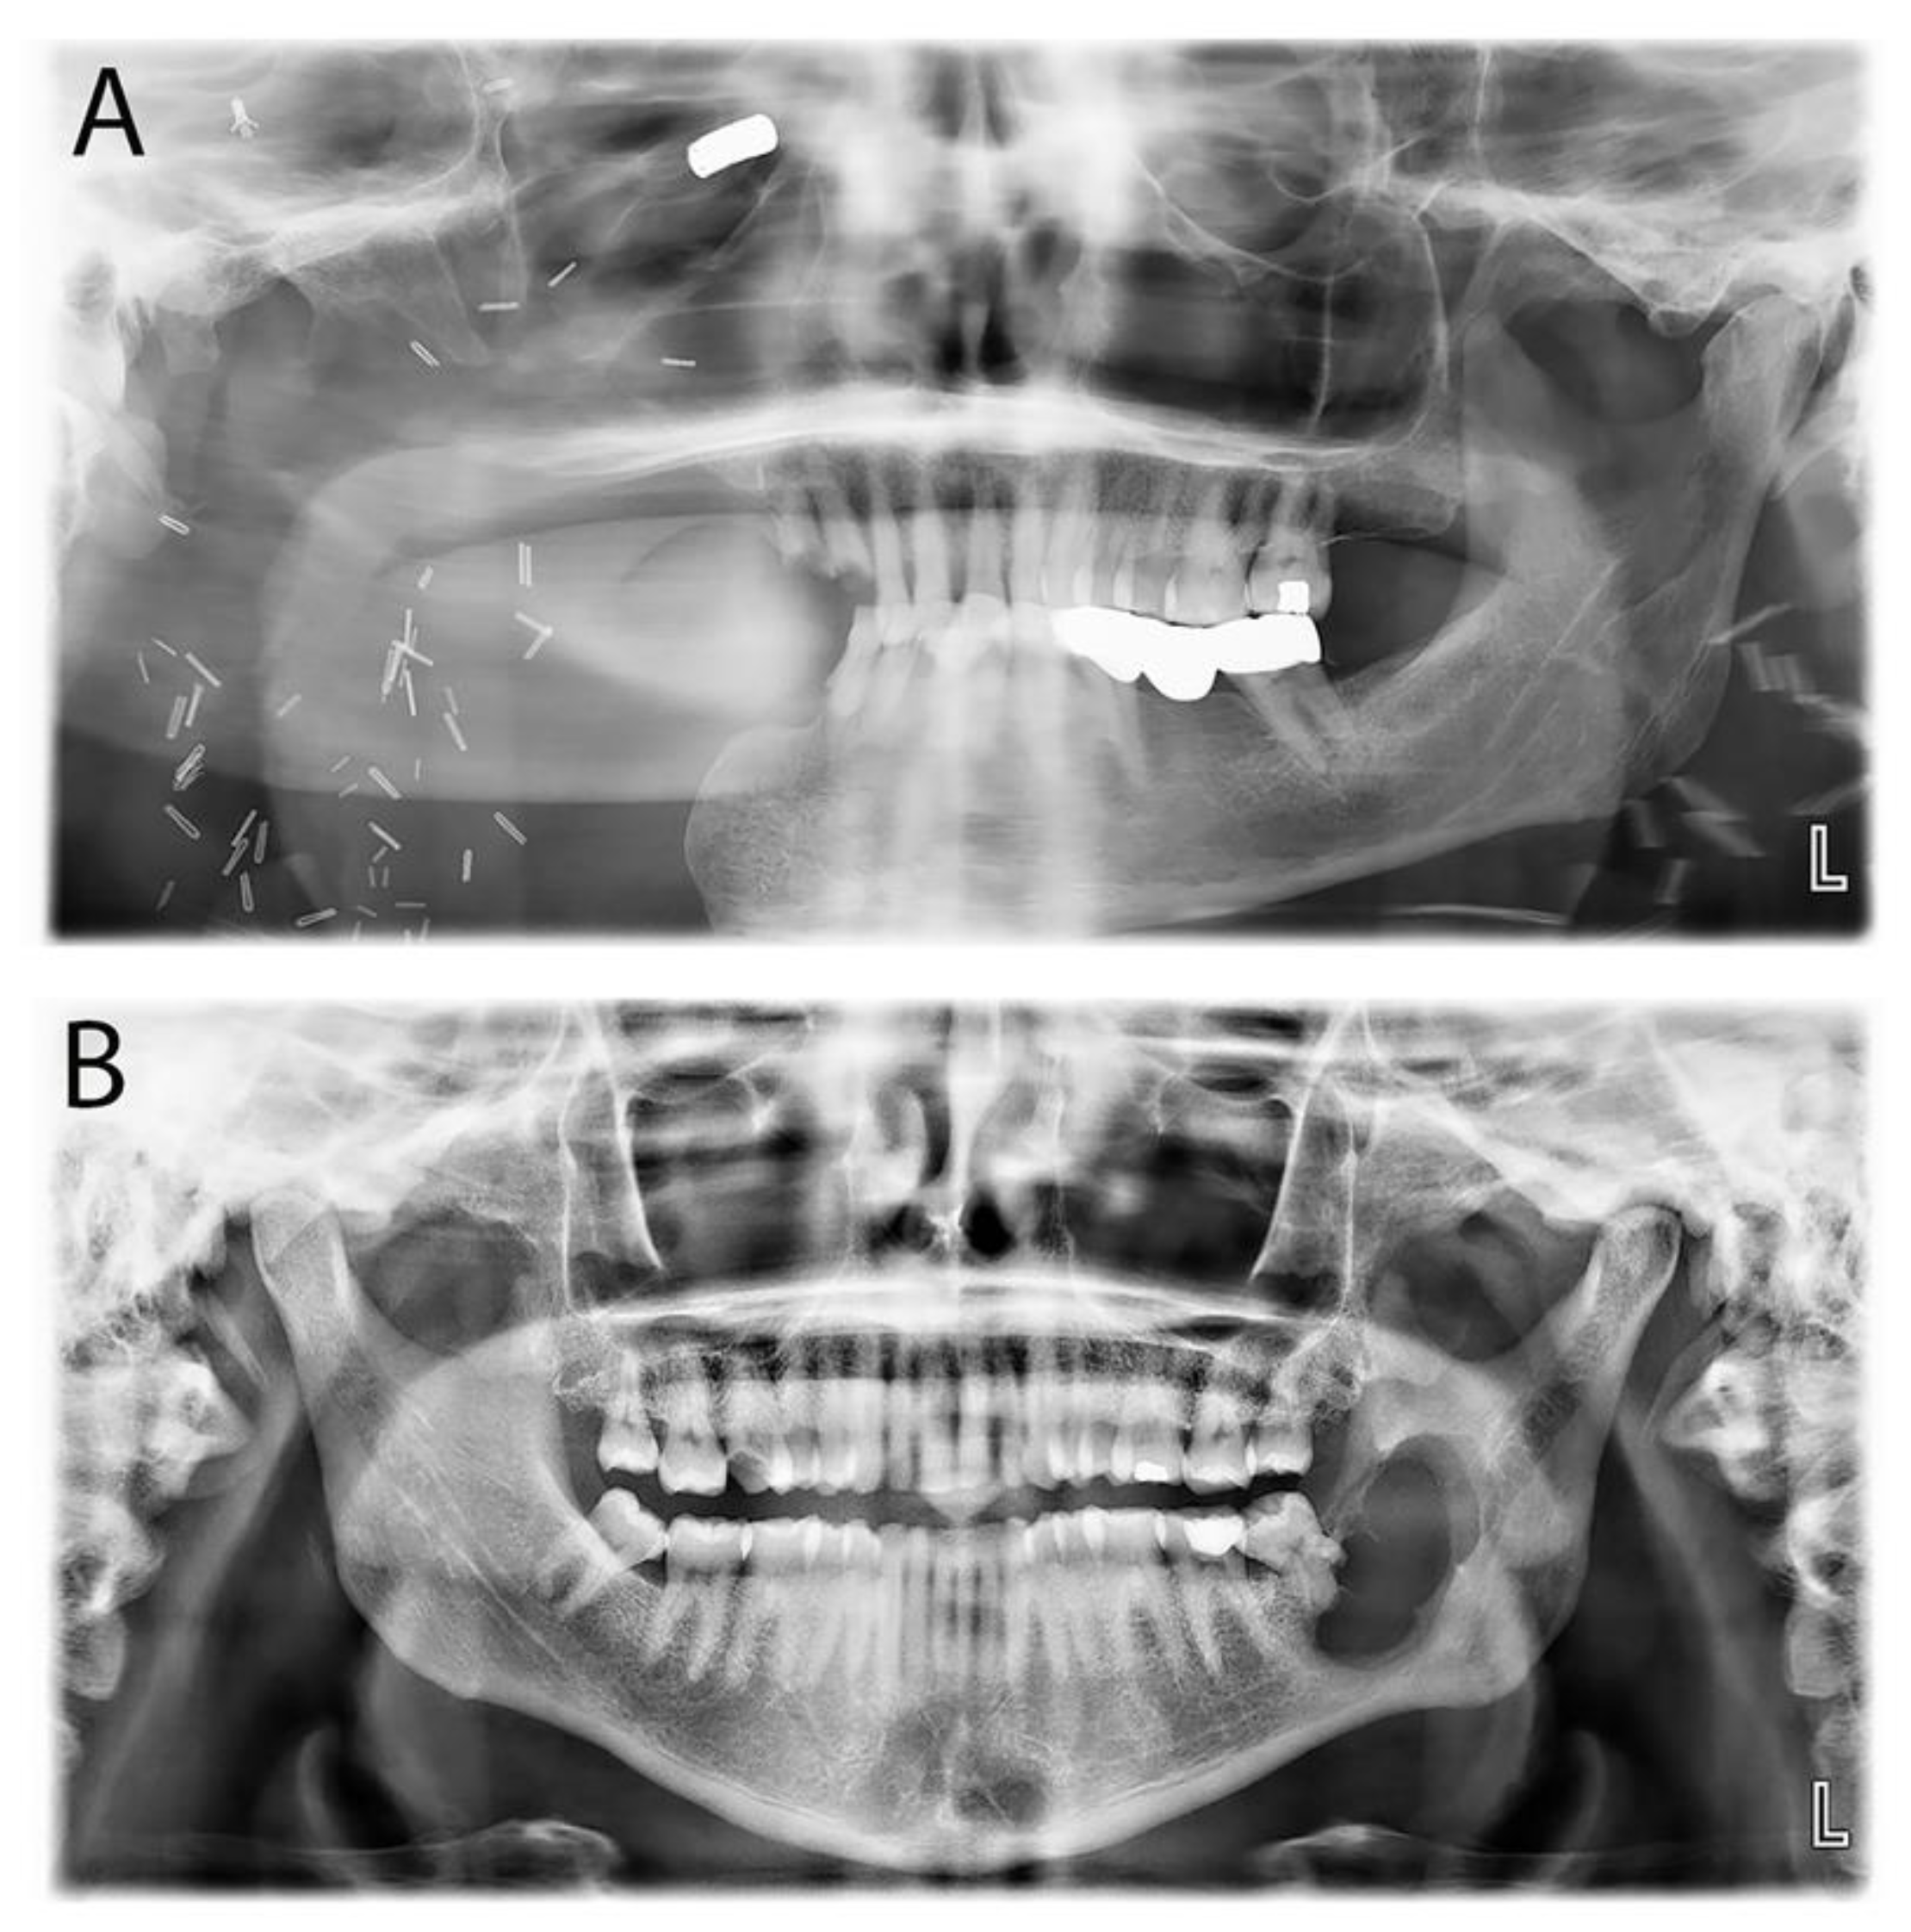

| Primordial odontogenic tumor | POT | Recently described mixed POT exhibiting primitive dental tissue with occasional hard tissue deposition. | Slowly growing lesion in the first two decades and always associated with an unerupted tooth, commonly the third molar. | Well-demarcated, unilocular, bilocular, or multilocular radiolucency associated with an unerupted tooth. |

| Primordial odontogenic tumor | 1 (1.1%) | 16 (N/A) | 1 (100%) | 0 | 1 (100%) | 0 |

| Primordial odontogenic tumor | 1 (1.2%) | 0 | 0 | 1 (100%) |